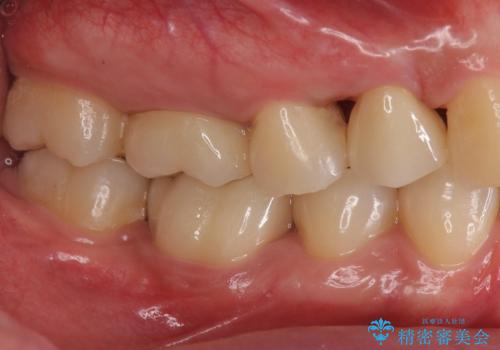

どうせなら1つ奥の銀歯も白くしたいとのご希望があり、2本ともセラミックにて治療をしていくことになりました。

- 右下6 仮歯+ジルコニアクラウン(スタンダード) 11000円×1本+110000円×1本 右下5 セラミックインレー 77000円×1本費用は治療当時の料金となります

虫歯治療に加え、奥の銀歯も同時にやり替えました。

精度の良いクラウンにやりかえることは今後の虫歯リスクを減らすことにつながります。